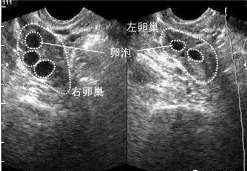

查看全文多囊卵巢综合征吃柠檬好吗? 多卵巢综合征一般多见于育龄期的女性,大部分表现为月经的不规律,肥胖,大多由于内分泌 […]